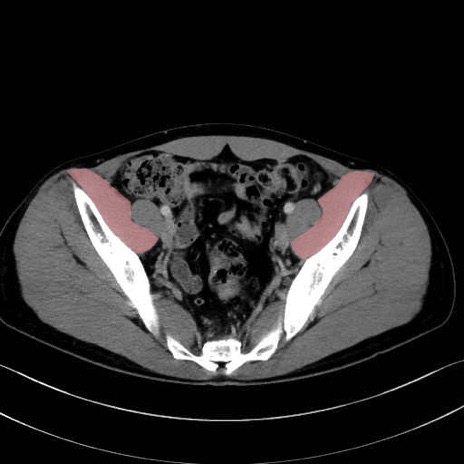

腸骨筋 (Iliacus)